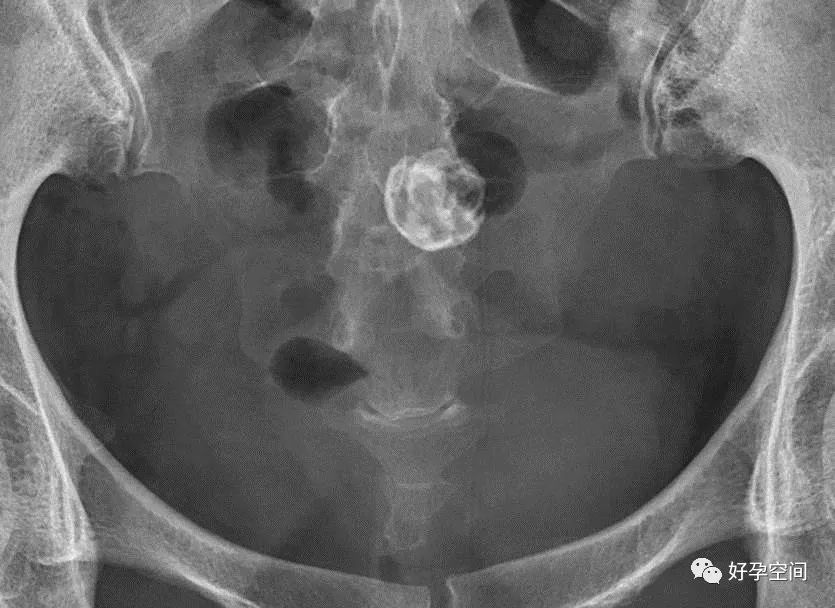

7、畸胎瘤钙化

盆腔内见牙齿状高密度钙化影